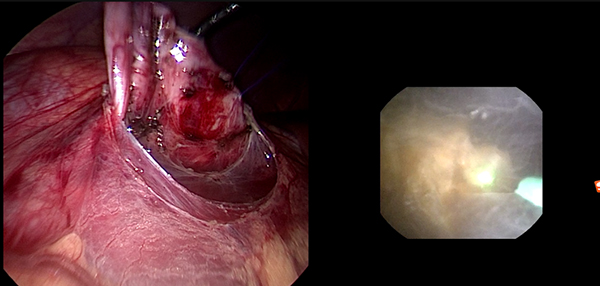

一名8岁女性儿童因血尿检查发现左肾输尿管积水并左输尿管末端结石入院治疗,检查发现患儿为输尿管末端狭窄合并左肾结石。由于患儿输尿管末端狭窄可经气膀胱腹腔镜手术,无法处理左肾结石,并且输尿管末端狭窄无法行输尿管软镜手术。经全科讨论后,决定在患儿行气膀胱腹腔镜输尿管再植的同时联合输尿管软镜进行左肾激光碎石。手术在吴荣德教授指导下,由刘伟主任医师、杜国强副主任医师等共同完成。气膀胱腹腔镜下切除左侧输尿管末端狭窄,经尿道置入输尿管软镜经输尿管末端进入,在下盏内见一大小约0.8×0.7cm黄褐色扁圆形结石,经输尿管软镜置入钬激光光纤予以碎石。碎石后行左侧输尿管膀胱再植术(Leadbetter术式)。患儿术后恢复良好,顺利出院。后期患儿规律复查,未再出现血尿、腹痛等不适症状。